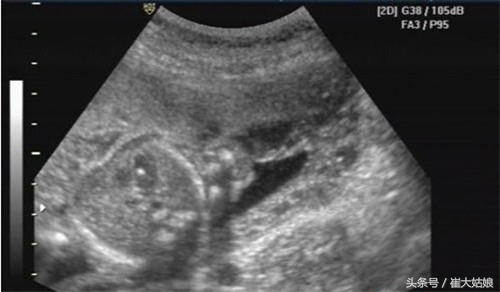

我进去后心里还有点紧张,躺下后一直盯着医生的手,没想到宝宝竟然配合得很,医生说终于有个看清楚的了。医生看得很认真,我担心说话会让他分神,一直也没有说话。过了一会医生问我唐筛做了吗,结果正常吗,我说正常,低危。这时他说,检查出胎儿左心室有个2mm强光点,需要看一下我的唐筛报告。我第一反应就是,强光点是什么鬼,是说心脏有问题吗?是心脏病吗?我一边找报告一边问医生。医生说,有强光点一般怀疑是宝宝心脏还没发育健全,也可能是胎儿染色体异常,但是唐筛结果低危,一般没什么问题。回诊室医生也说应该没事,约了两周后再复查,看是不是会自行吸收掉。

一般情况下,NT和唐筛的结果是低危,没有必要做羊水穿刺进一步检查。医生也一般建议两三周以后再去复查,看看强光点有没有变大,若是消失的话会更好,即使不消失,只要不增大就没有问题。很多宝宝直到出生还能看到强光点,只要不是心脏有构造性问题就没事。大排畸左心室强光点在亚洲人中很常见,发生概率高达30%。单纯的强光点,对没有其他症状的唐筛低危产妇是不具有临床意义的。